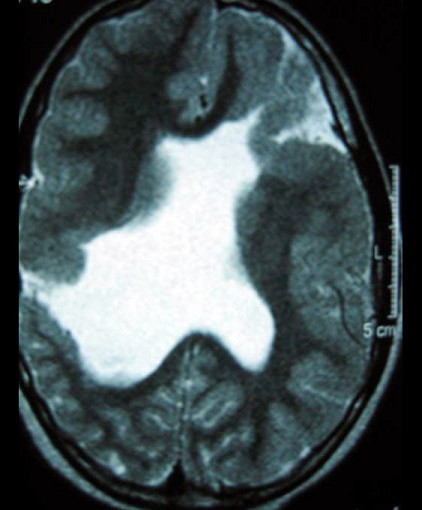

9岁男孩,有癫痫发作史,MR表现如图,首先考虑以下哪个疾病 ( ) TLC-00501.jpg TLC-00502.jpg TLC-00503.jpg TLC-00504.jpg

• A.胼胝体发育不全

• B.脑灰质异位

• C.Dandy-Walker综合征

• D.脑裂畸形

• E.无脑回畸形